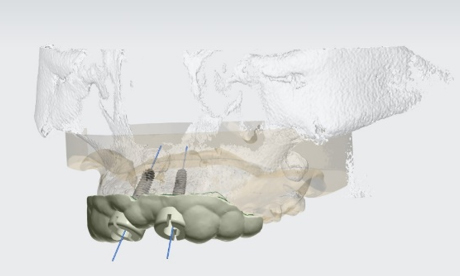

3D 디지털 모의수술을 통한

임플란트 과정을 미리보다3D CT 분석을 통한 검진 결과를 바탕으로 환자 맞춤형 가이드를 미리 제작합니다. 이후 3D 컴퓨터 모의수술을 통해 경로를 결정하고 소량 절개 시술로 잇몸 손상과 통증을 줄입니다. 오차는 줄이고 정확성은 높힌 디지털 임플란트 입니다.

오스카55플란트치과는 무치악 환자의 틀니 스캔부터

플래닝, 가이드 제작, 시술, 최종 보철에 이르는

전 과정을 FULL DIGITAL 디지털화 하여 정밀함을 높였습니다.